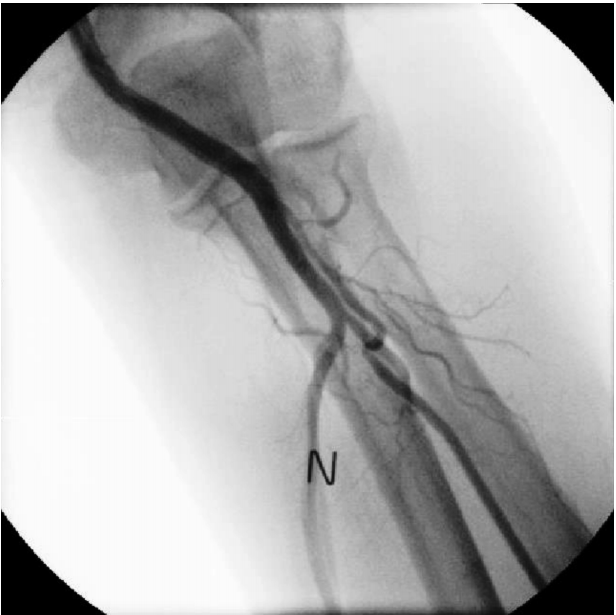

A 69-year-old male was hospitalized for coronary intervention after evaluation by computed tomography (CT) revealed critical stenosis of the distal left circumflex artery (LCX).The patient underwent coronary angiography via the left radial route with a 6 French (Fr) sheath (Terumo Corp., Tokyo, Japan) inserted using standard techniques. The left radial angiography showed a minor degree radial artery spasm (Fig. 1A). After injecting 200 μg of nitroglycerin via the radial artery, coronary angiography was successfully performed with 5 Fr JL4 and JR4 diagnostic catheters. The distal LCX lesion was similar to the lesion revealed by the coronary CT scan (Fig. 2A); therefore, PCI was deemed the best treatment option. During insertion of a 6 Fr extra back-up (EBU) guiding catheter (Medtronic, Dublin, Ireland) over a 0.035-inch standard guidewire, the catheter encountered resistance and the patient complained of pain in the left forearm. After removing the 6 Fr EBU guiding catheter, radial angiography was performed by injecting diluted contrast agent through the side port of the sheath. The contrast agent revealed perforation and extravasation of contrast agent into the surrounding tissue (Fig. 1B). A 5 Fr EBU was able to pass the perforated segment over the remaining 0.035-inch standard guidewire. PCI was performed successfully with balloon angioplasty and a 2.75 X 18-mm stent (Resolute integrity, Medtronic, Dublin, Ireland) (Fig. 2B). After removing the guiding catheter, radial angiography was performed via the sheath’s side port. The procedure showed that the perforation was sealed and that there was no contrast agent extravasation (Fig. 3).The patient was discharged after 48 hours without any local vascular complications, with a patent radial pulse, and no local hematoma.

Figure 3.

Sealed perforation after percutaneous coronary intervention with a 5 Fr EBU guiding catheter. N, nitroglycerin; EBU, extra back-up.